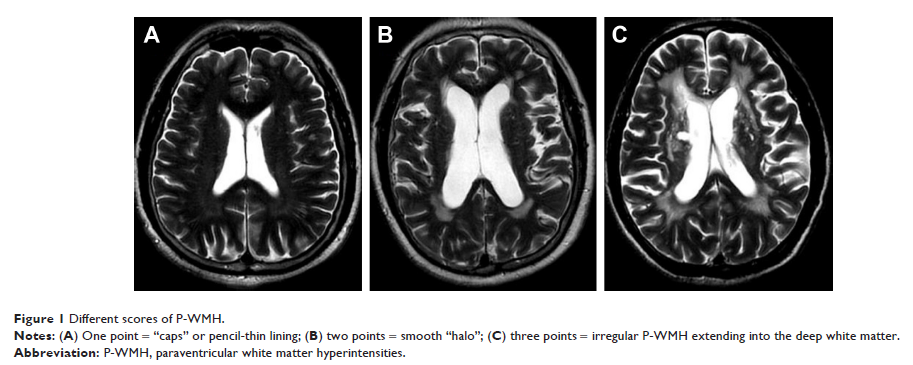

- 作者:Ling Yu, Lei Yang, Xiaoyu Zhang, Junliang Yuan, Yue Li, Shuna Yang, Hua Gu, Wenli Hu, Shan Gao

- 期刊:Clinical Interventions in Aging